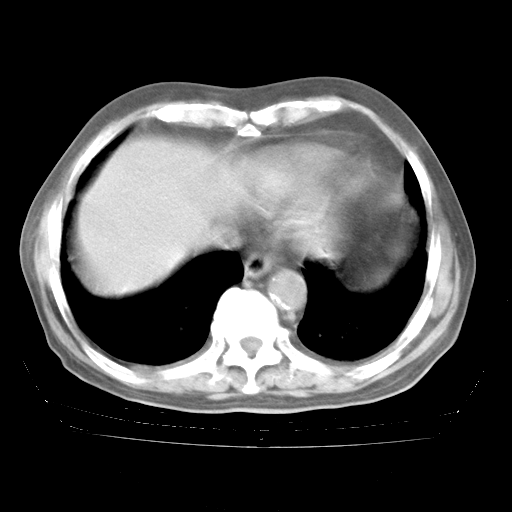

4月28日肺部CT

腹部B超:胆囊壁增厚,肝、胆、胰、脾、肾无异常,肠系膜淋巴结、腹膜后淋巴结无增大。

1、108#的是4月14日的胸部CT(发此贴时还没看着28日的CT)。14日的胸部CT其实已经出现改变(如108#所述),个人认为28日的胸部CT除纵膈窗疑似有双侧胸膜增厚或少量胸积液(可行胸部B超明确)外,与4月14日对照病变有所加重;2、已经给予“异烟肼、利福平、乙胺丁醇”抗痨治疗?如果是,甲强龙80mg可缓慢减量;如果环磷酰胺已停用,暂不使用;3、中性粒细胞92%,明显升高,目前体温情况?注意合并细菌感染可能,使用左氧氟沙星情况下,是否联用B-内酰胺类抗菌药物?另外是查免疫全套非风湿全套。